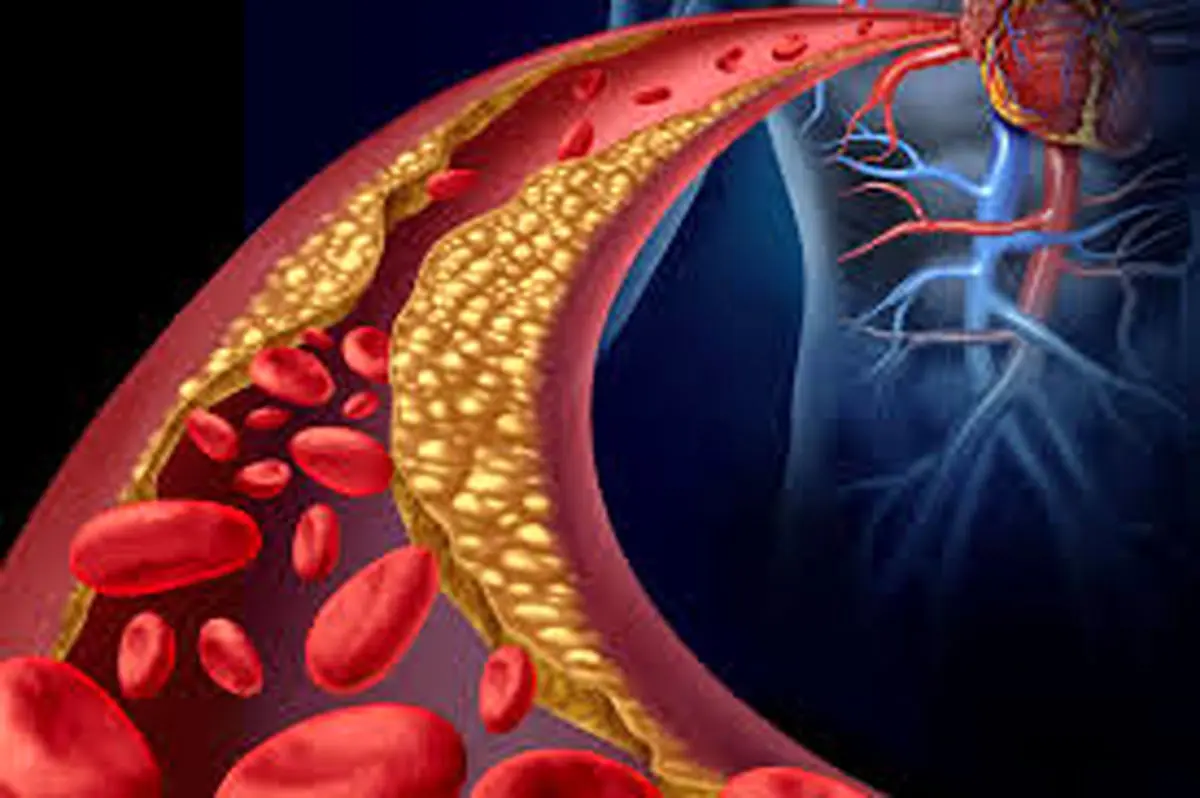

یک مطالعه جدید نشان داده است این قرص توانسته در افرادی که با وجود مصرف داروی موجود، همچنان در معرض خطر بالای حمله قلبی هستند، میزان کلسترولِ عامل گرفتگی رگها را کاهش دهد.

کلسترول LDL زمانی به بیماریهای قلبیعروقی دامن میزند که ذرات آن در دیواره رگهای خونی رسوب کند و باعث آترواسکلروز (تصلب شرایین) شود؛ فرایندی که میتواند به حمله قلبی و سکته مغزی منجر شود.